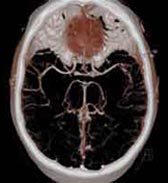

„CT“ ist die Abkürzung für Computer-Tomographie. Mit dieser Röntgen-Untersuchungsmethode können detaillierte Bilder vom Inneren Ihres Körpers erstellt werden. Die CT wird angewandt, wenn Ihr Arzt genauere Informationen benötigt, die herkömmliche Röntgenuntersuchungen nicht liefern können. Ein besonderer Vorteil der CT sind die kurzen Untersuchungszeiten auch bei großen Untersuchungsbereichen. Die Röntgenstrahlen werden in Ihrem Körper entsprechend der Dichte des Gewebes geschwächt, vom Detektor erfasst, elektronisch aufbereitet und im Computer in Grauwerte umgerechnet. Durch die sogenannte Fensterung lassen sich unterschiedliche Gewebearten (z. B. Lunge, Knochen, Weichteile) besonders detailreich darstellen. Mit mathematischen Verfahren können beliebige Schnitte und dreidimensionale Bilder berechnet werden.

Die CT ist ein Röntgendiagnoseverfahren, das im Gegensatz zu klassischen „Durchleuchtungen“ dreidimensionale digitale Informationen aus dem Körper liefert. Die Röhren-Detektoren-Einheit in der Gantry rotiert schrittweise oder permanent (Spiral-CT) um Ihren Körper, der auf dem Tisch vorgeschoben wird. Die Radiologie Darmstadt setzt einen Qualitätsstandard, indem alle CT-Untersuchungen mindestens an einem modernen 16-Zeilen-Mehrschicht CT-System durchgeführt werden; am Standort Alice-Hospital sogar an einem 256-Schichten FLASH-CT. Mit mathematischen Verfahren können beliebige Schnitte und dreidimensionale Bilder berechnet werden.